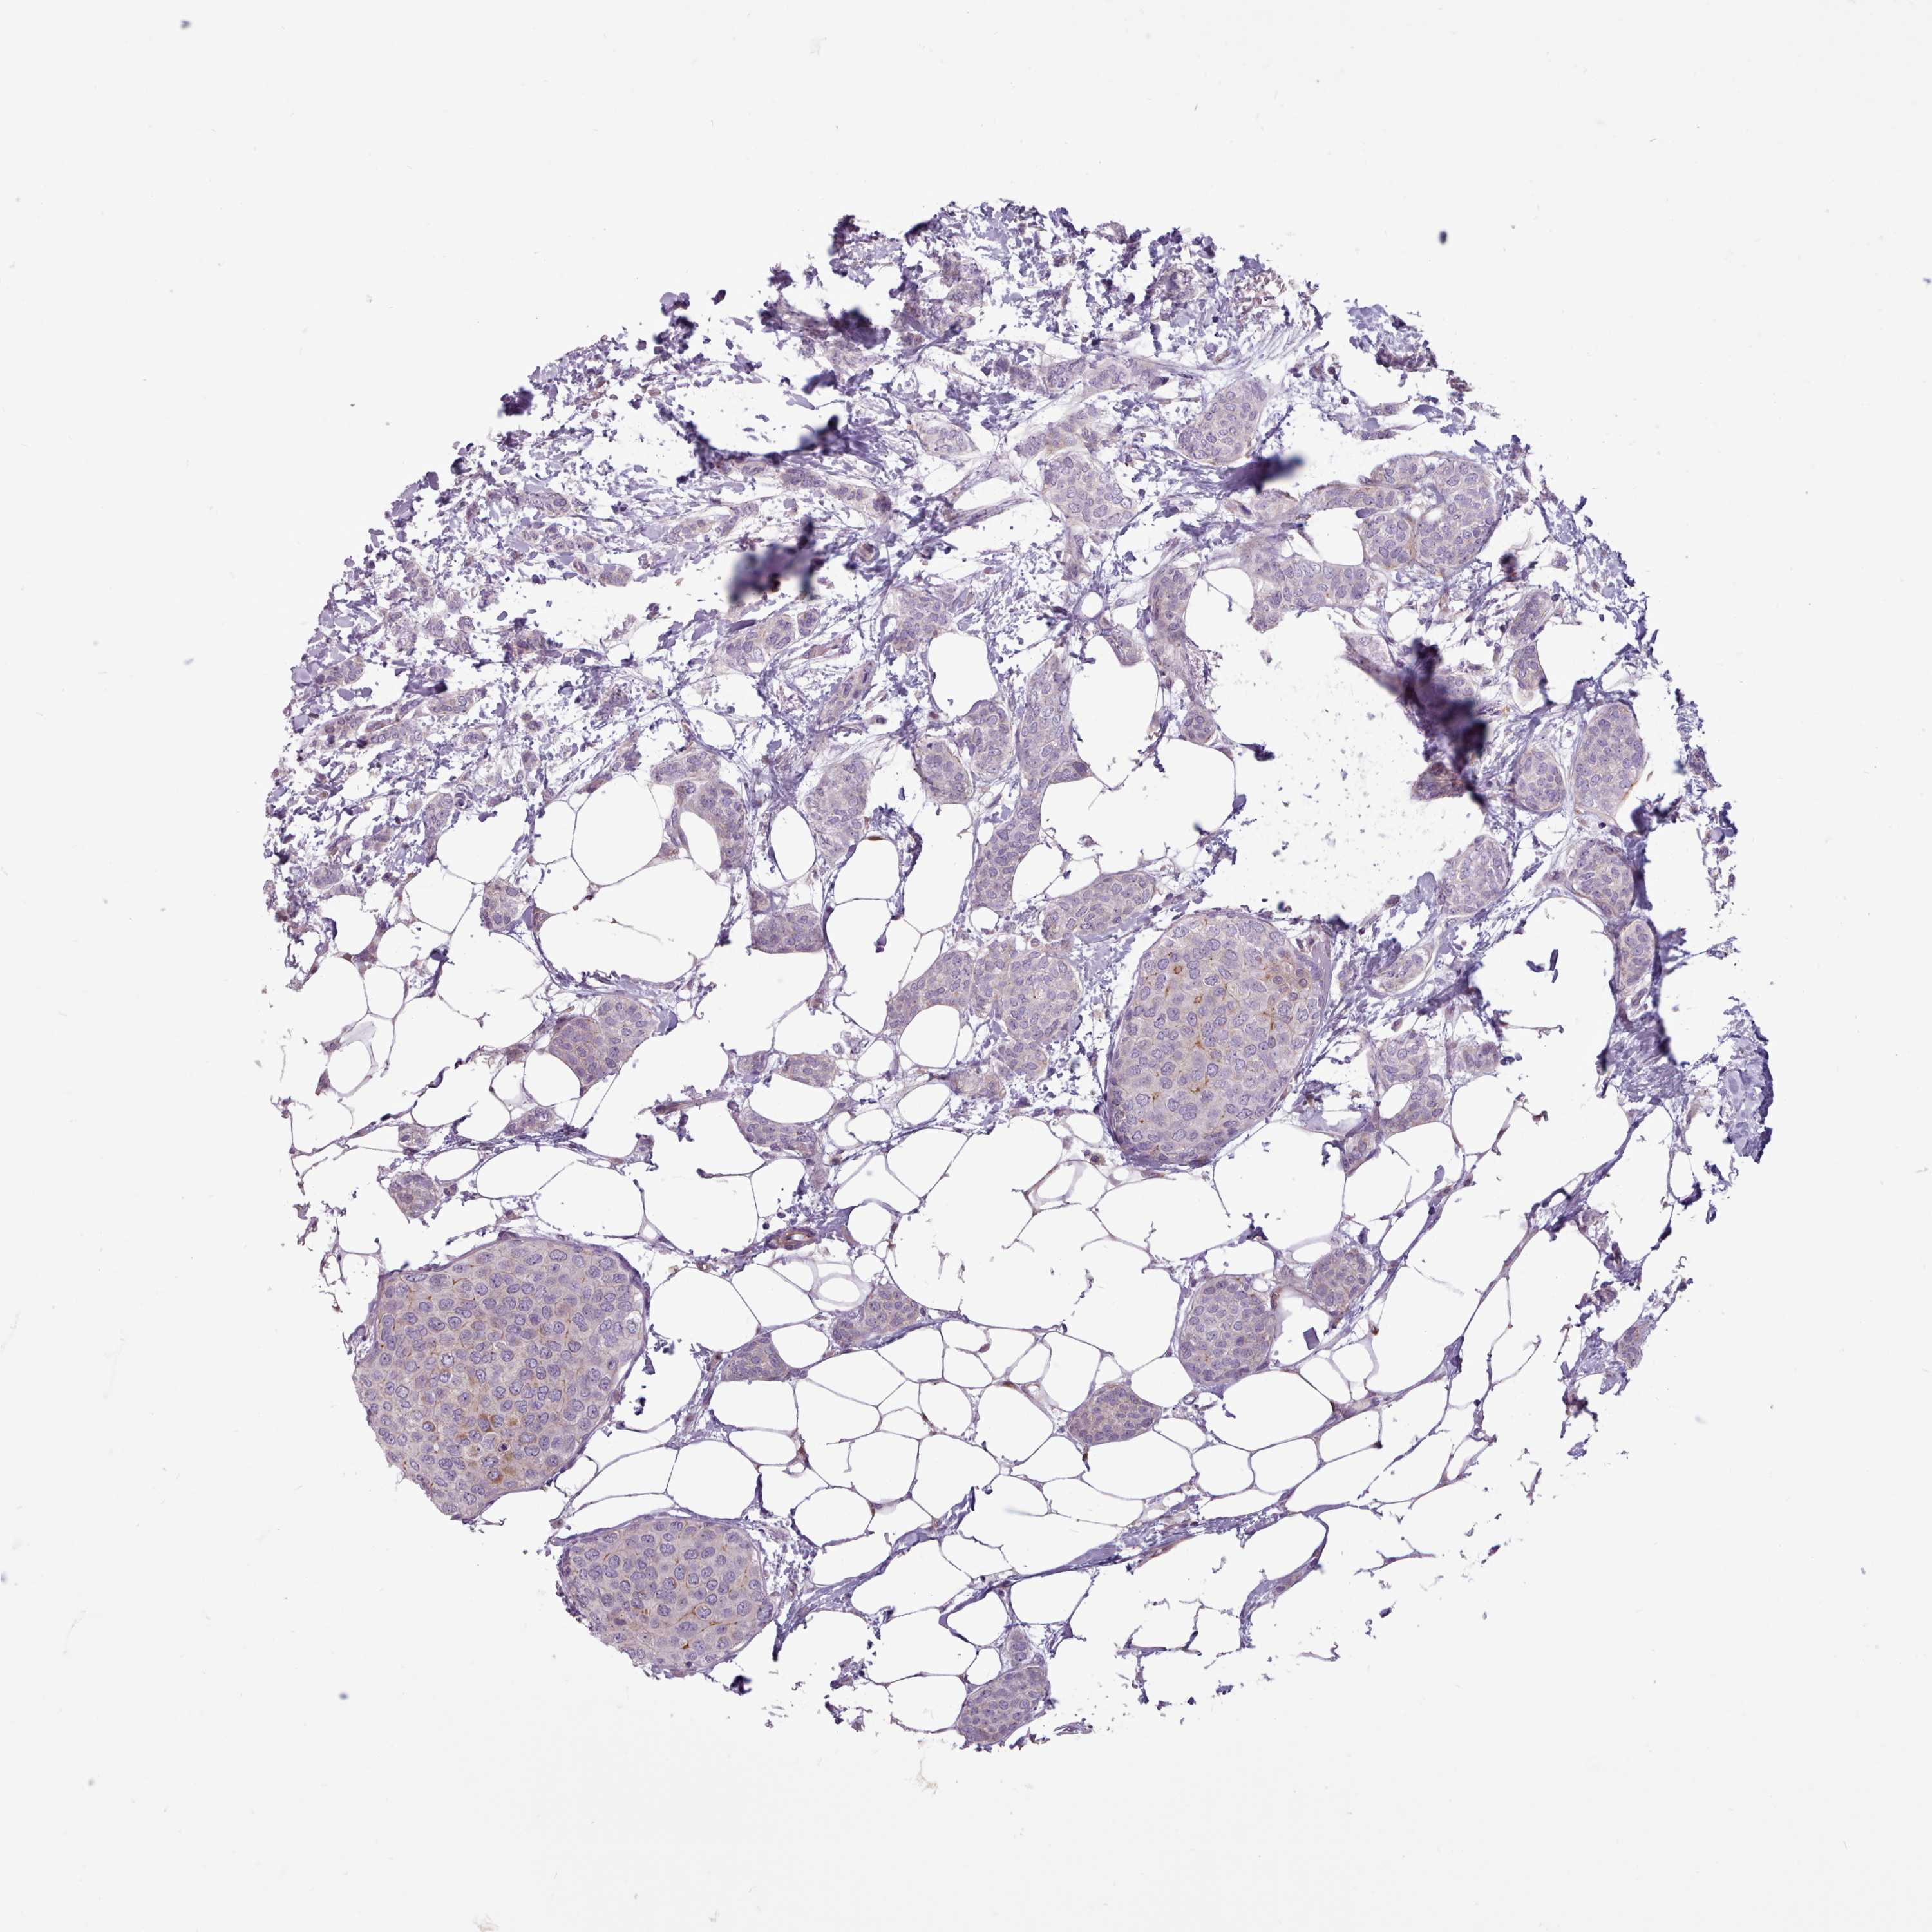

CANCER BREAST CANCER Show tissue menu

Breast cancer

Human cancer